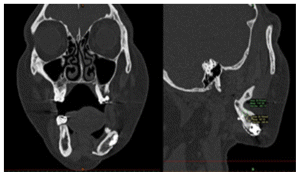

Subsequently, seven months later, on 10/17/12, she presented endodontic problems in the previously treated teeth and lost the second lower left molar after the revision, radiographic changes were seen in the panboramic X ray. (Figure 3) An incisional biopshy was taken,10 months 15/08/2013 based on the diagnosis of the biopsy, a CT scan was taken and a stereolithography model was developed for the surgery of the central ossifying fibroid by mandibular resection.

The patient after surgery continued under observation and could not continue with her treatment due to the Covid epidemic, resuming the treatment on 03/02/2014 for the reassessment by CT the new bone formed in the area of surgery was observed by two programs Blues Sky Bio and Mimics of Materialise the values in Hounsfield units were determined in each of the CT slices at the sites planned for the placement of three implants, the values ranged from 209 U. Hounsfield to 1372 U. Hounsfield (Figs, 15,16,17,18).